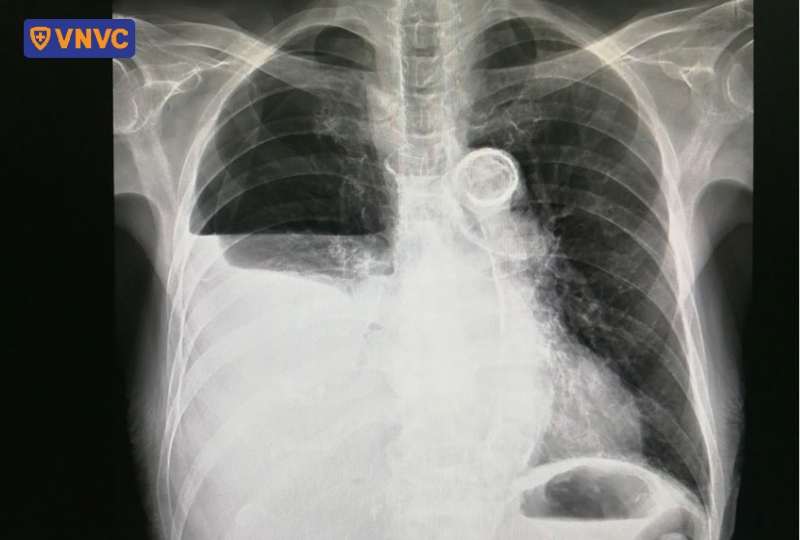

Tràn khí màng phổi

Tràn khí màng phổi xảy ra khi không khí lọt vào khoang màng phổi, chèn ép phổi và gây đau ngực đột ngột kèm khó thở, ho khan, đôi khi tím tái. Bệnh có thể xuất hiện tự phát hoặc sau chấn thương, thủ thuật hoặc trên nền bệnh lý hô hấp mạn tính.